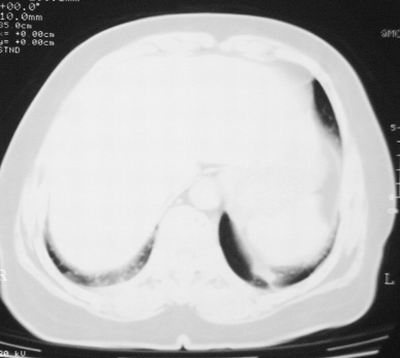

本次复查胸部ct

左下肺软组织块影,有分叶、毛刺、空泡及胸膜牵拉征,左下肺周围性肺癌。

左肺下叶周围型肺癌,支持!(软组织肿块+分叶+毛刺+空泡+胸膜凹陷征)

左下肺软组织密度影,可见分叶,边缘可见毛刺征,胸膜增厚,强烈要求左下肺周围型肺癌

左下肺后基底段实性肿块,周围有毛刺,病变周围有肺气肿,与降主动脉间有条带状影相连,病灶4年前查体发现,纵隔内未见肿大淋巴结。考虑.肺隔离症,建议增强扫描与周围型肺癌鉴别。